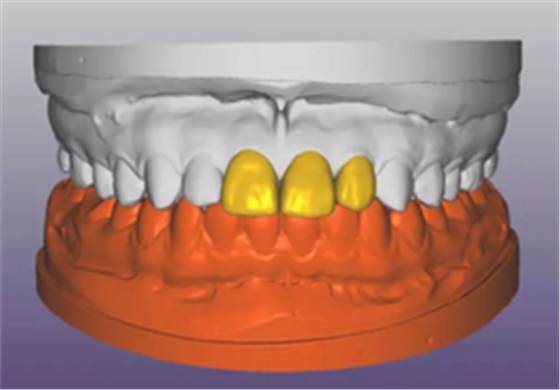

(1)术前准备。拍摄临床照片、拍摄轻开口位CBCT(NewTom)、取聚醚印模灌制超硬石膏模型。 构建数字化模型并设计修复体:将超硬石膏模型在口外扫描(Identica? Hybrid),获取软硬组织表面形态,构建数字化模型,确认咬合情况。根据 天然牙残根颈部形态设计修复体颈部形态,使修复体颈缘轮廓与原有天然牙 一致;按正常牙弓弧度与覆 、覆盖关系,结合红白美学等原则确定修复体 的三维形态。最后,导入患者面部照片,确认模拟修复效果。 设计种植体位置并制作多级导板:利用Segma设计软件,将CBCT数据 和模型扫描数据进行配准,调入模拟修复效果数据,以修复为导向设计种植 方案,设计种植体螺丝孔开口从修复体舌窝处穿出,最终实现螺丝固位的一 体化基台冠修复。根据种植体信息设计多级导板,参考修复体形态设计导板 植入区颈缘外形,打印生成种植导板(Segma),并安装金属引导环。 设计并制作临时修复体:如前所述,按照美学效果和咬合关系设计临 时冠外形,颈部形态与模型龈缘轮廓一致,保证临时修复体在术后可以封闭 拔牙窝。3颗临时冠为连冠,龈外展隙适当加大,为术后软组织生长提供一 定的空间。在临时冠近两侧邻牙的切角处预留翼板,保证临时冠戴入时可以 找到准确的位置。以铣削的方式加工临时冠(Segma),待种植体植入后 将其在口内粘接于临时基台上。

图4 构建数字化模型并设计修复体